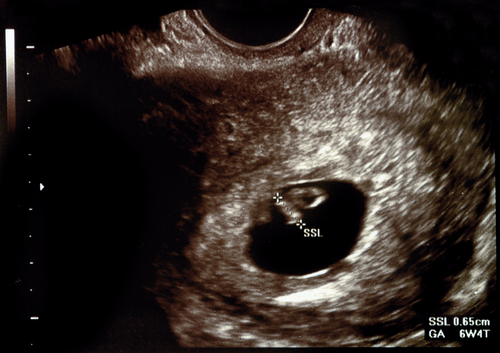

胎嚢(たいのう)とは赤ちゃんを包んでいる袋の事をさします。妊娠7週の子宮を超音波画像で見ると、黒い袋のようなものが見えますが、それが胎嚢です。下のエコー写真では胎嚢の中に「胎芽」と呼ばれる赤ちゃんが確認できますね。

胎嚢は医学用語でGS(Gestational Sac)と略されるので、超音波画像の写真のGSの所を見ると、赤ちゃんの胎嚢の大きさを知る事ができますよ。

この時期の胎嚢は、1日約0.5~1mmずつ成長すると言われています。妊娠7週の胎嚢はおよそ2~4cm程の範囲が正常な経過と言えます。